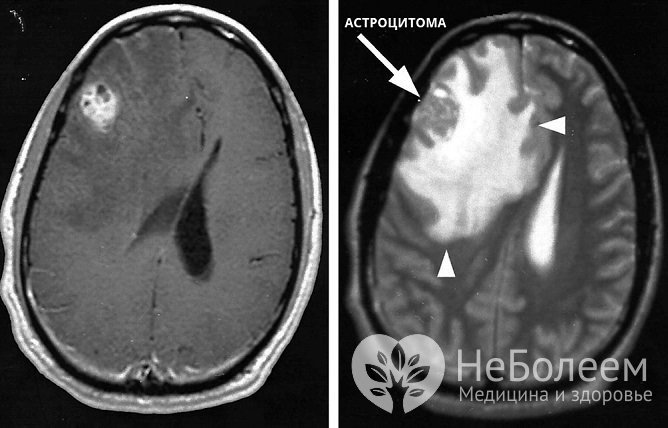

Для диагностики астроцитомы и ее особенностей проводится ангиографияПервичное инструментальное обследование при подозрении на астроцитому головного мозга состоит в проведении электроэнцефалографии (ЭЭГ) и эхоэнцефалографии (ЭхоЭГ). Выявленные изменения являются показанием для направления на магнитно-резонансную или компьютерную томографию головного мозга.

Для уточнения особенностей кровоснабжения астроцитомы выполняется ангиография.

Точный диагноз с определением степени злокачественности опухоли можно поставить только по результатам гистологического анализа. Получить биологический материал для проведения этого исследования возможно при стереотаксической биопсии или в ходе оперативного вмешательства.